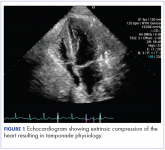

ArticleMassive liver metastasis from colon adenocarcinoma causing cardiac tamponadeAuthor:Halthore et alPublish date: February 18, 2018Read More